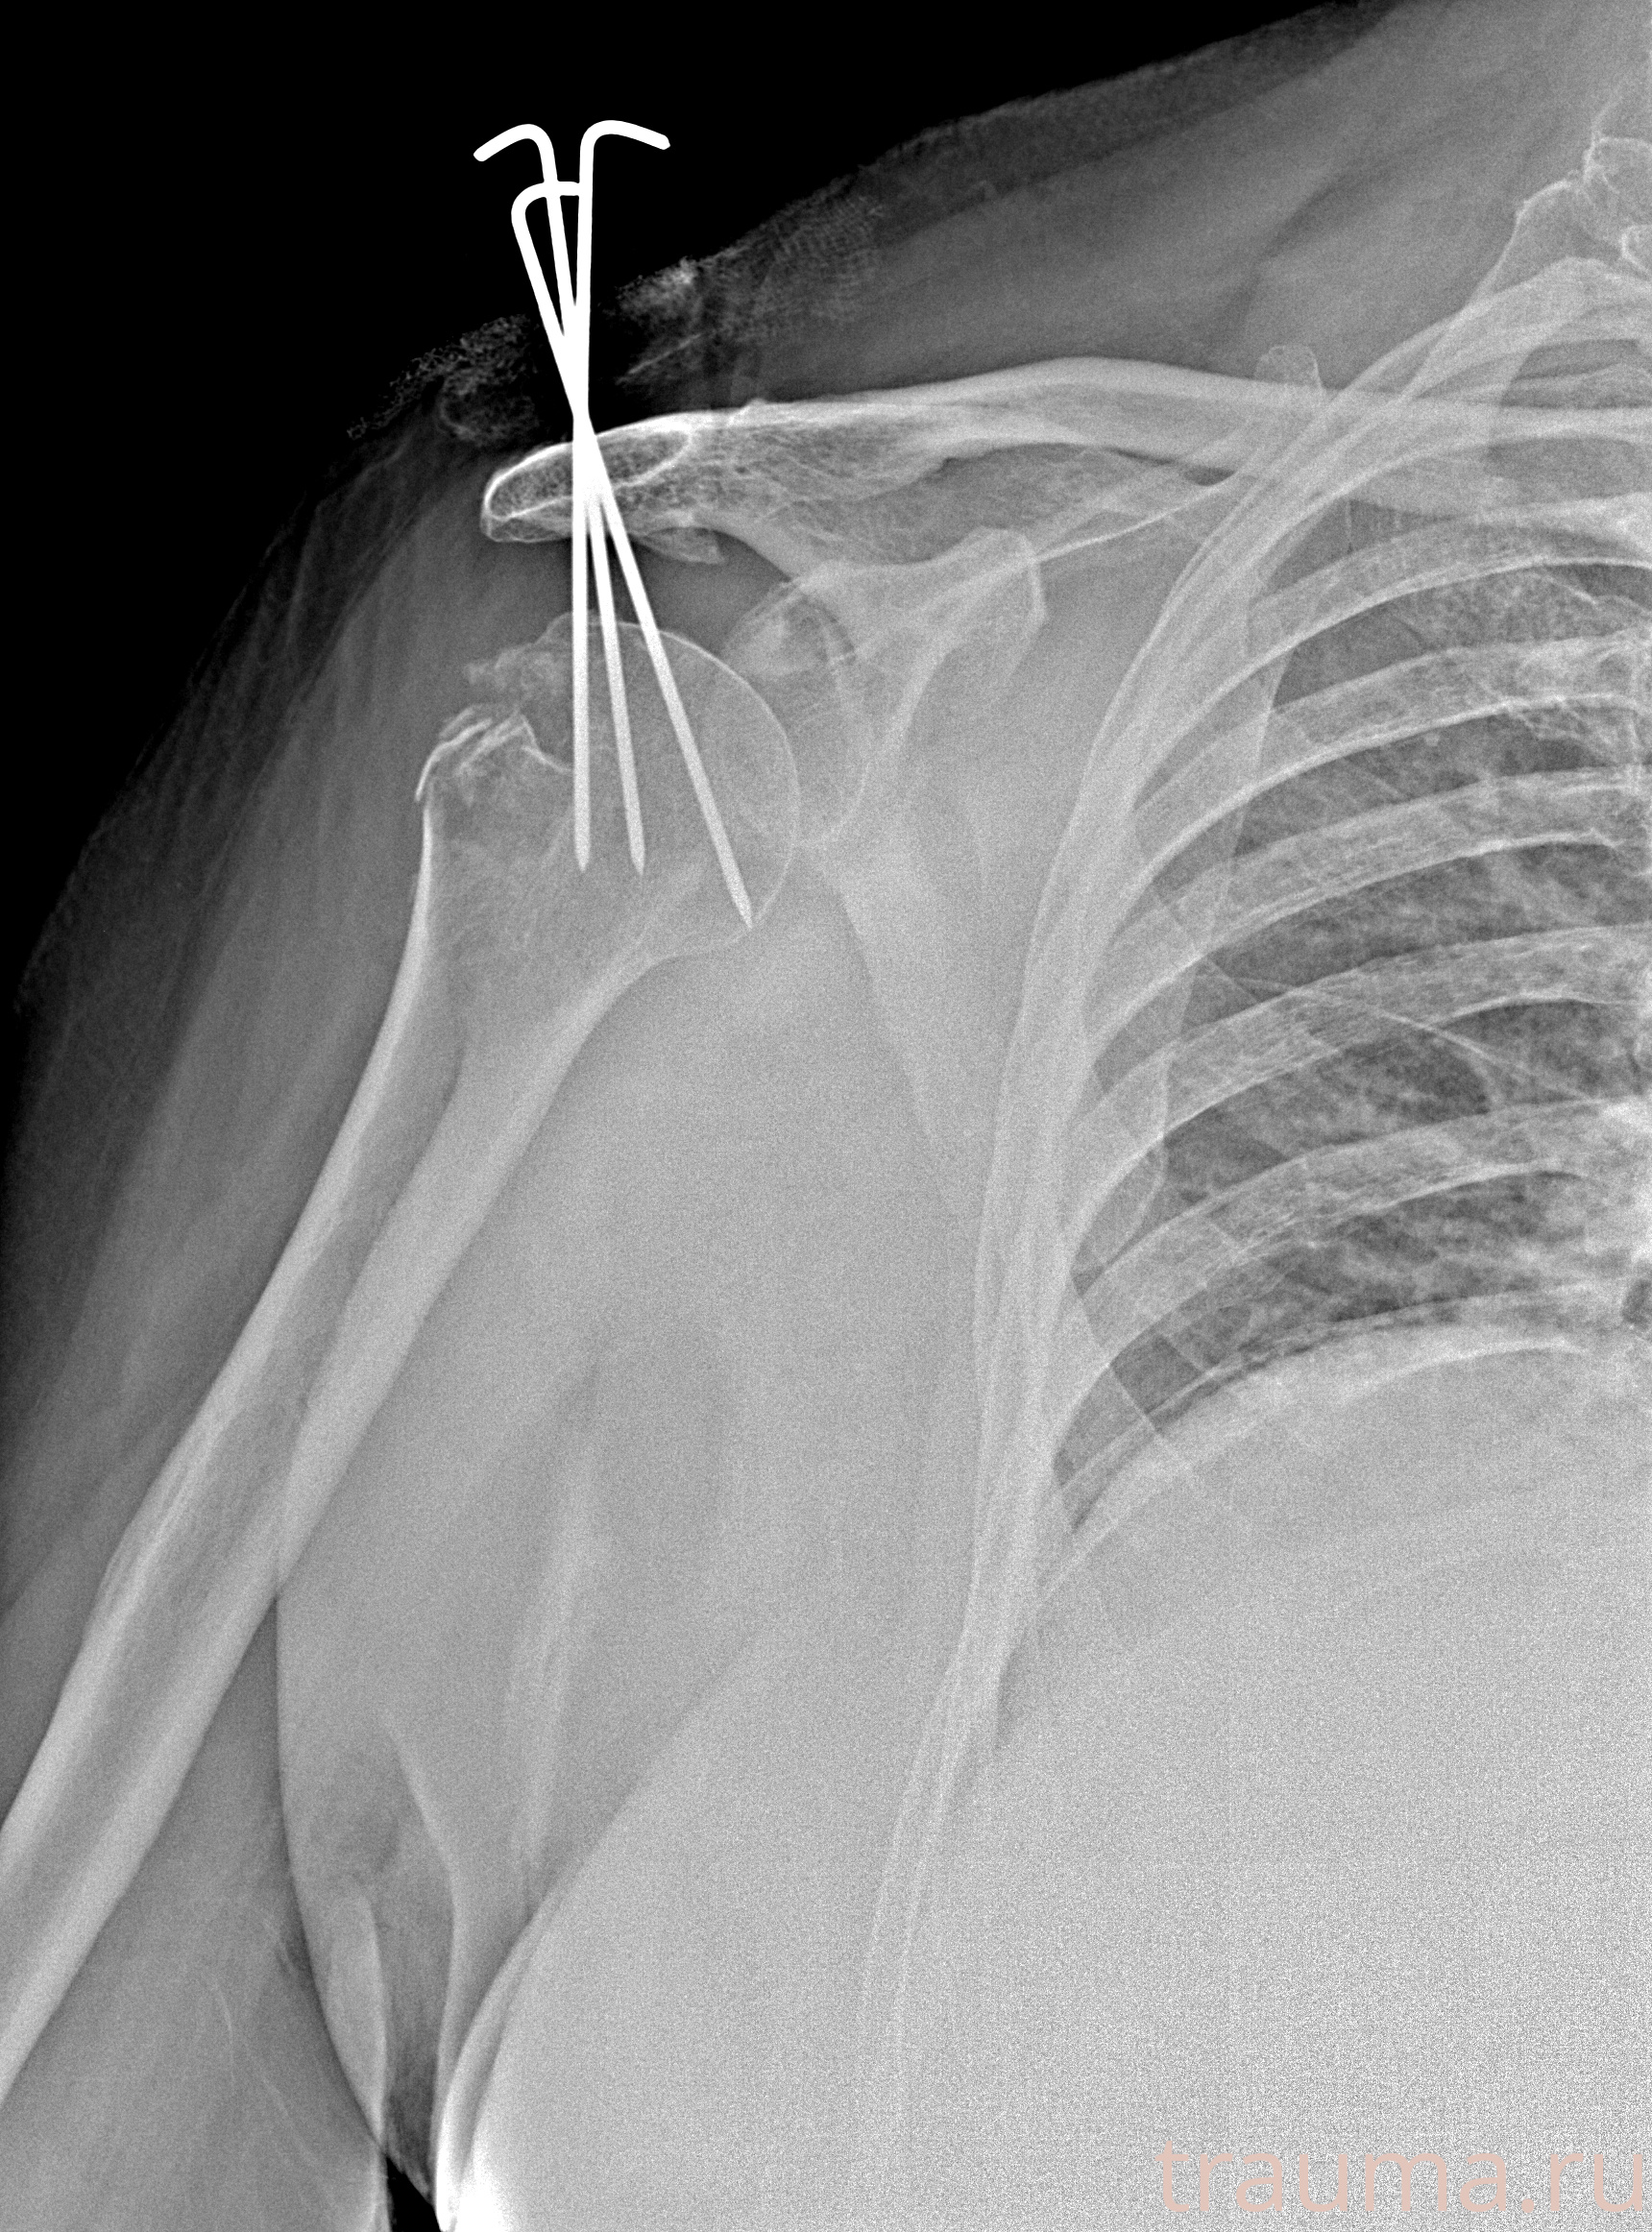

Рентгенограммы